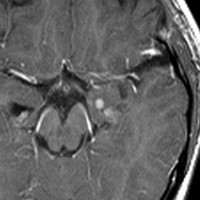

10才の時に,複雑部分発作(症候性てんかん)で発症しました。吐き気を感じた後に嘔吐して意識が遠くなる(意識減損)という症状であり,側頭葉てんかんです。脳波では左側頭葉に徐波律動がみられました。発作は頻回でしたがカルバマゼピンの投与で抑制されていましたが,MRIで腫瘍が発見されました。

左内側側頭葉グリオーマ mesial temporal glioma と呼ばれる腫瘍です。左の扁桃体,海馬鉤,海馬,海馬傍回に腫瘍が浸潤しています。T2強調画像とFLAIRでまだらな高信号で境界ははっきりしません。mass effectが少なく,増殖増大傾向のある腫瘍には見えないのが特徴です。下段右のように部分的にガドリニウム増強されるのも神経節細胞腫の特徴かもしれません。しかし,神経節膠腫,乏突起膠腫,乏突起星細胞腫(グレード2)なども疑われます。

手術中の脳波モニターでは,棘波が上側頭回の後方(ウェルニッケ領域)に存在し,深部電極刺入で海馬近傍にも棘波がみられましたが,もちろん上側頭回や海馬の切除はしませんでした。扁桃体 amygdala と海馬鈎 uncus の腫瘍部分のみを切除して手術を終了しています。海馬と海馬傍回には腫瘍を残しました。上のMRIは,その後6年経過した後のものですが腫瘍は全く同じ大きさです。抗てんかん薬も止めて,発作は全く生じていません。このような腫瘍は,扁桃体と海馬鉤を摘出することで,発作を完全に止めることができることがあります。ですから,最初の手術では,リスクのある余分な脳切除をしません。